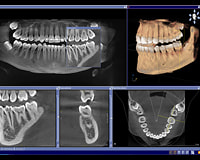

3D CT scan

直径8×高さ8㎝で160μmの高精細な画像を提供します。ORTHOPHOS XG 3Dは、たった1回のスキャンで全顎の撮影が可能で、一画面で広い診断領域を観察することができます。

日常診断の様々な診査・診断に使用することができます。

迅速な診断と低被ばくを同時に実現している装置です。